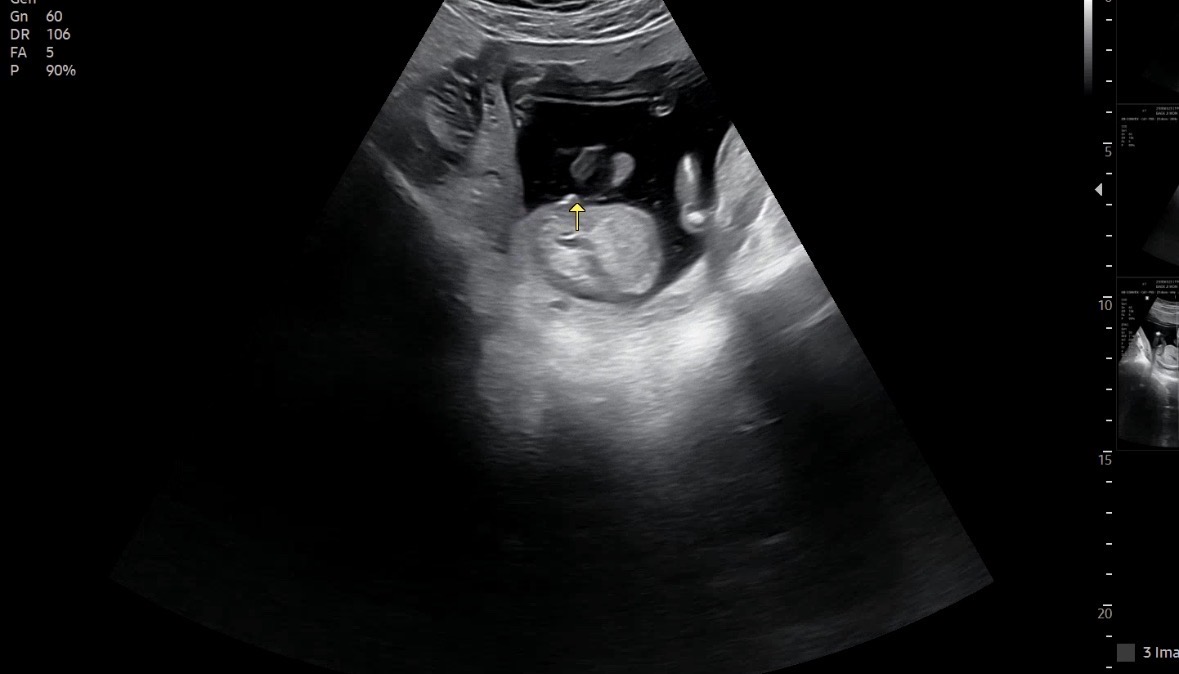

이게 미사일이 맞는건가용..?

의사쌤이 뭐가 보이네요~ 이러는데 저는 왜 다른 분들처럼 슝! 나오는 미사일이 안보이는 걸까요..? 은근 현실 부정중인지 ㅎ